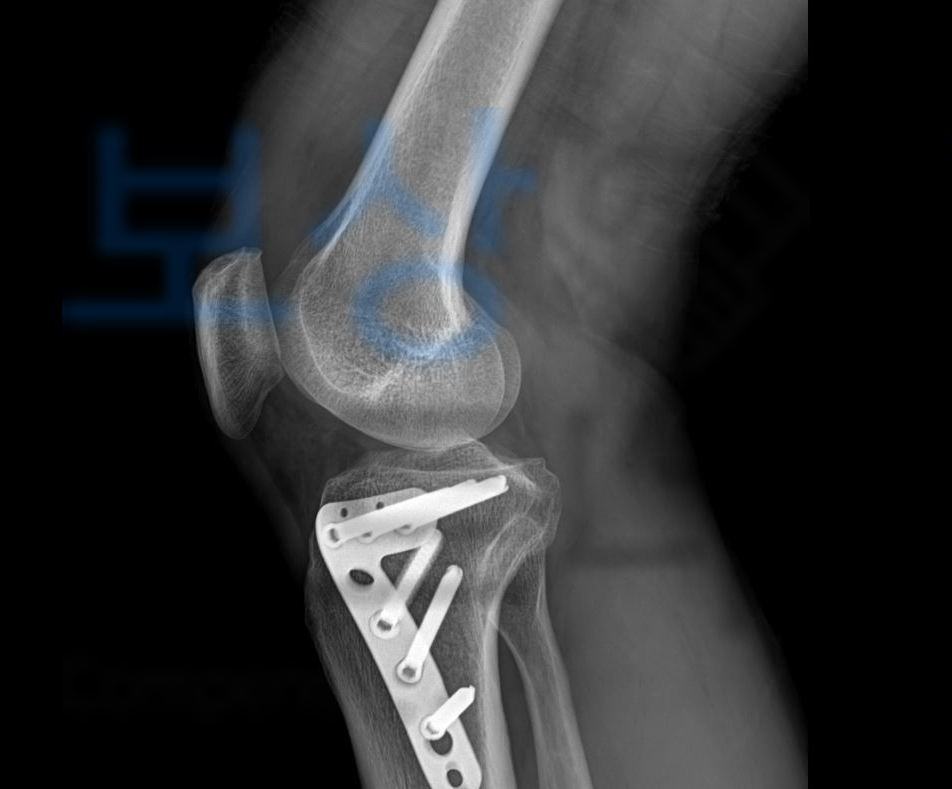

정@@님은 건설 현장에서 자재가 무릎에 떨어져 무릎뼈가 골절되는 사고를 당하셨습니다.

위 사고로 정@@님은

관혈적 정복 및 금속내골정술, 관절경술 즉 핀 고정술을 하셔야 했는데요,

위와 같이

무릎뼈 골절로

슬관절의 기능 장해 12급

인정받았습니다.